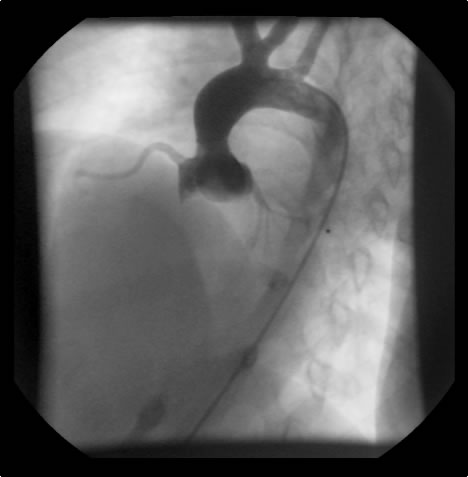

An asymptomatic, 5-year-old, 18-kg boy known by genetic testing to have Williams syndrome on physical examination had a IV/VI harsh systolic ejection murmur and no diastolic murmur. Preoperative echocardiogram showed an aortic root dimension of 2 cm and the dimension at the level of stenosis in the ascending aorta was 8 mm. Peak echocardiogram gradient was 70 mm Hg with a cardiac catheterization gradient of 50 mm Hg. The child had no peripheral pulmonary artery stenosis.

Preoperative transesophageal echocardiogram in long-axis view shows ascending aorta with aortic valve to the left. The markers indicate the aoritc root dimension to be 2.0 cm and hte mid portion of the stenosis to be 0.8 cm.